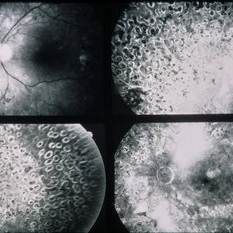

PDR

Jan 24 2014 by Howard Schatz, MD

64-year-old white female. Proliferative diabetic retinopathy.